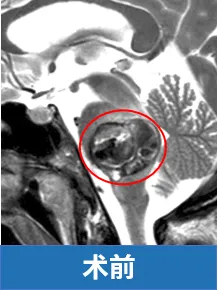

而Laura的影像片上,更棘手的问题藏在脑干深处:她的海绵状血管瘤长在脑桥上,这个病变已经把原本紧凑的脑桥撑得像个鼓起的气球,周围密密麻麻的神经纤维被挤得变了形。

最终手术顺利,术后一年,Laura笑着进到诊室复查,明显可以看到她的面神经和外展神经功能已基本恢复。“我很感恩现在的一切,我能帮孩子梳头发,还能自己做饭。”Laura说着,抬手捋了捋头发,脸上的笑容自然又轻松。她的复查影像显示:脑桥区域没有残留病灶。